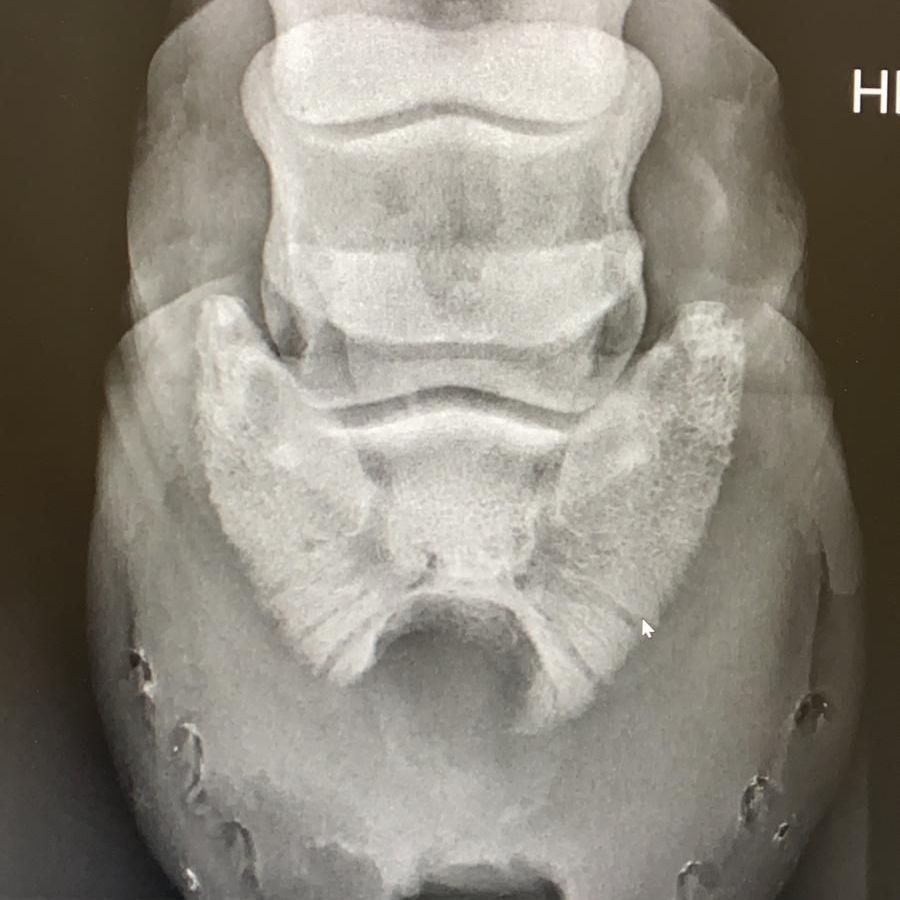

Auf den Bildern sieht man die Fehlstellung. Der Huf erst mit Dallmer-Korrekturfohlenschuh behandelt worden. Die Bilder unten zeigen die OP, wobei eine Schraube die Wachstumsscheibe einseitig fixiert. Ganz unten ist die zweite Phase zu sehen. Die Stellung hatte sich da schon deutlich gebessert. Ein mildere Korrektur mit Kunsthorn konnte somit vorgenommen werden.